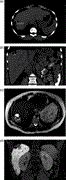

Massive retroperitoneal dedifferentiated liposarcoma in a young patient

Fernando X Moyon and others

Journal of Surgical Case Reports, Volume 2018, Issue 10, October 2018, rjy272, https://doi.org/10.1093/jscr/rjy272